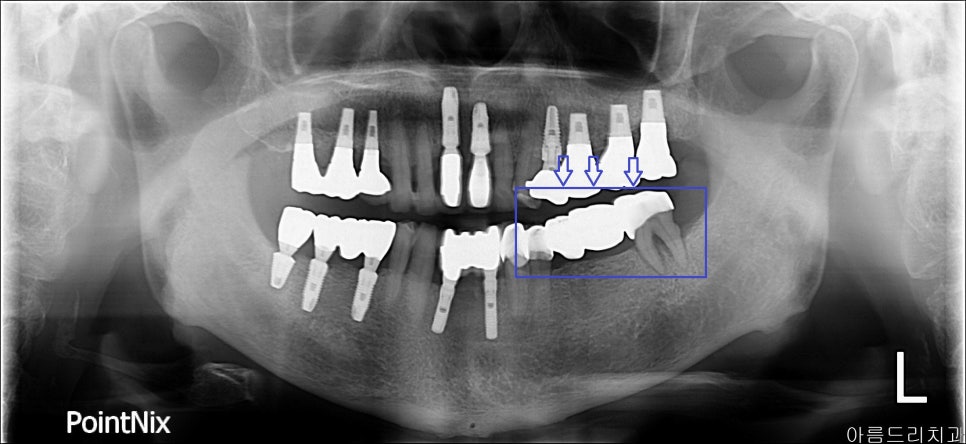

임플란트 시술 전 x-ray

임플란트 시술 과정_아름드리 치과_ x-ray